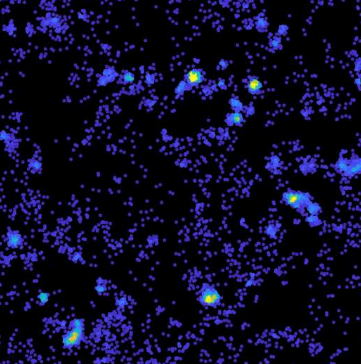

该团队由 CJCADR 主任 Jürgen Götz 教授和 Padmanabhan 博士领导,他们使用超分辨率显微镜来关注质膜——细胞与其外部环境之间的屏障。

“我们设法观察了非常接近质膜的单个 Tau 分子,以及它们如何在纳米级水平上移动和组织,”Padmanabhan 博士说。